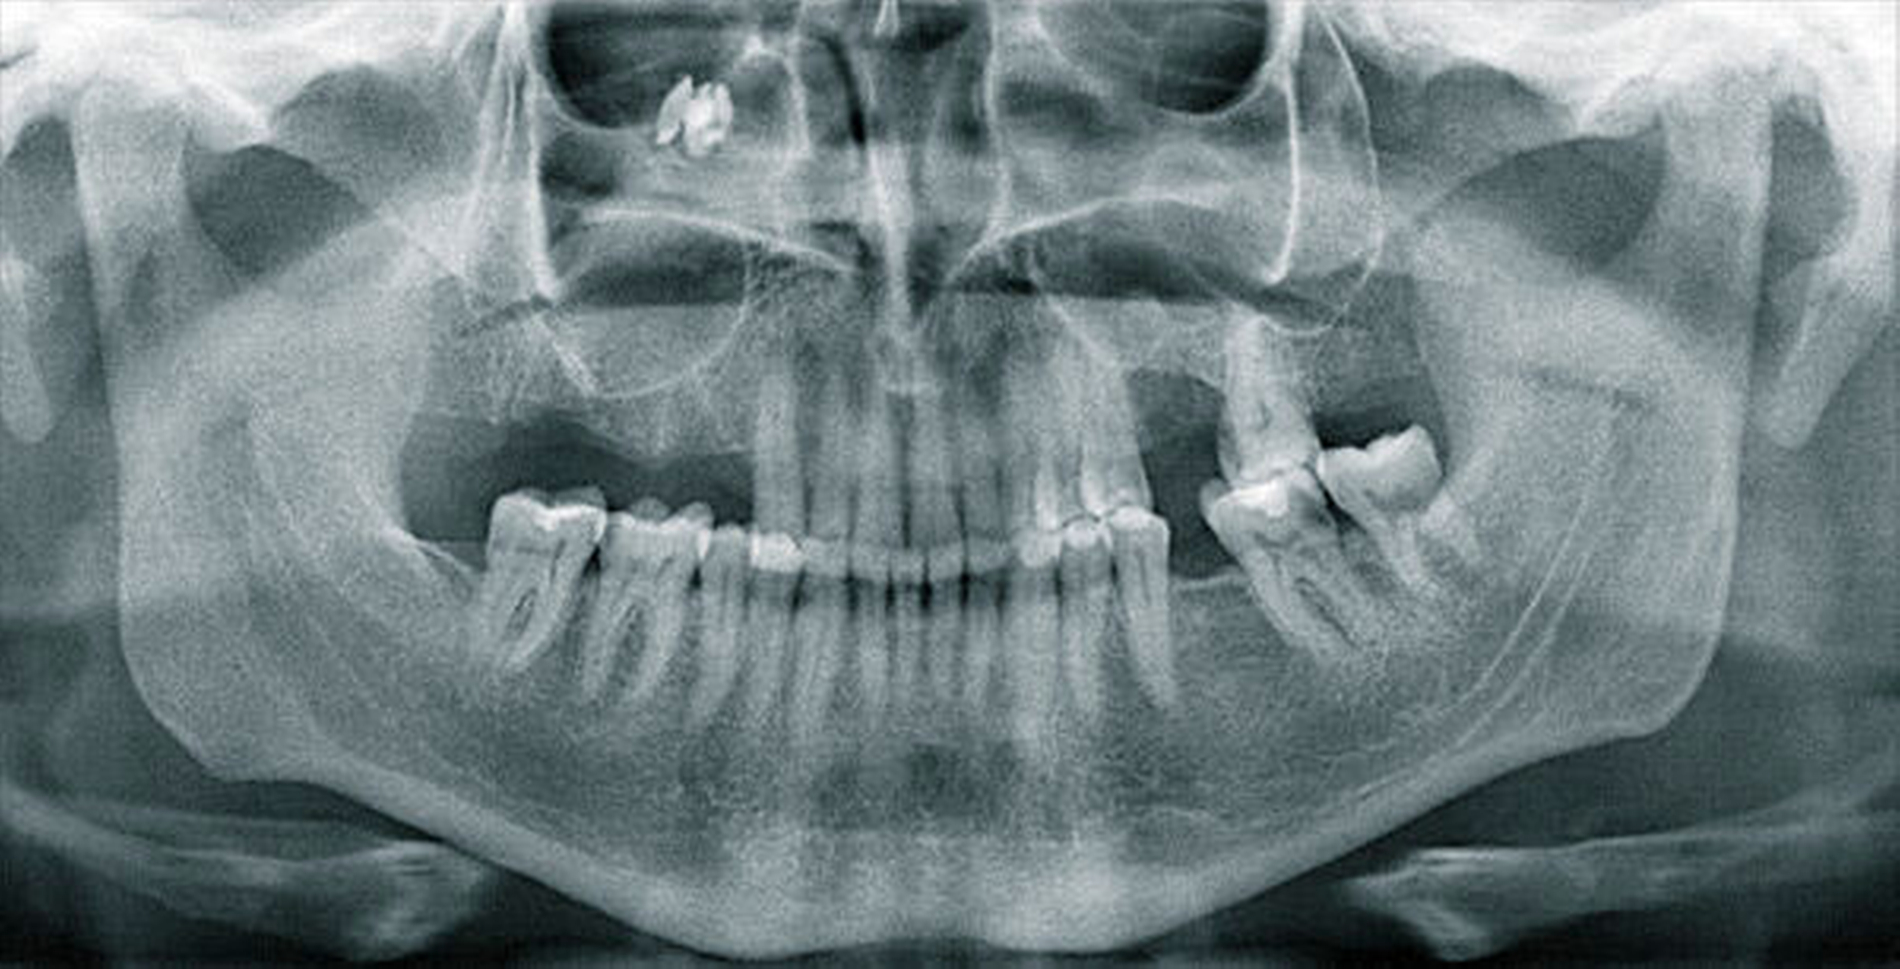

Das angefertigte Orthopantomogramm (OPT) stellte den aktuellen Zahnstatus mit dem Nebenbefund einer röntgendichten Verschattung im Sinne eines Fremdkörpers unterhalb des rechten Kieferhöhlendachs dar (Abbildung 1). Es folgte die Anfertigung eines NNH-CT zur genauen Lokalisierung des Fremdkörpers (Abbildung 2) für die anschließende OP-Planung.

In unserem Fall zeigte sich der röntgenopake Fremdkörper im OPT als Zufallsbefund. Zur genauen Lokalisation ist jedoch eine zwei- bis dreidimensionale radiologische Darstellung notwendig [Ferguson, 2014]. Bei der zweidimensionalen Darstellung bietet sich zum OPT ein Fernröntgenseitenbild und bei der dreidimensionalen ein DVT, NNH-CT sowie im Fall von nicht ferromagnetischen Fremdkörpern auch ein MRT an.